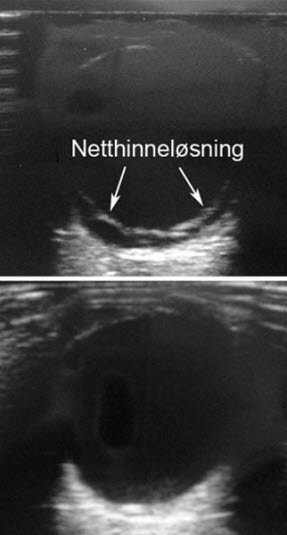

Ultralyd av netthinneløsningSykehistorien er ofte karakteristisk med beretningen om at pasienten opplever det som at det dras ned en gardin foran synet. Ved bruk av øyekikkert (oftalmoskop) kan diagnosen stilles, eller legen får mistanke om at noe er galt som krever videre utredning.